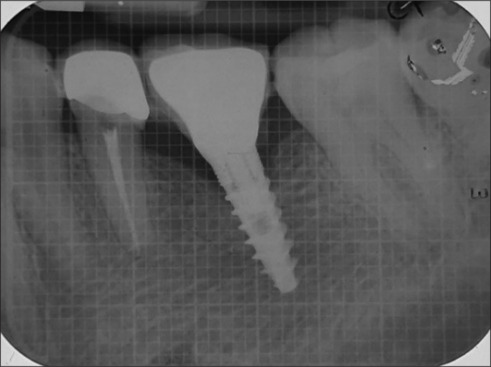

Purpose: The present investigation assessed the success of narrow diameter implants (NDI) supporting a single crown in the molar region of the jaw.

Materials and methods: A total of 40 patients (>20 years) requiring implant supported crown in the molar region were recruited. A total of 20 patients received NDI (3.5 millimeter (mm), and another 20 received standard diameter implants (SDI), ≥3.75 mm. Crestal bone level, probing depth (PD), implant mobility, and bleeding on probing (BOP) were recorded at baseline, 6, and 12 months.

Results: The control group showed 0.29 ± 0.17 of mean crestal bone loss at 6 months and 0.51 ± 0.21 at 12 months (P < 0.001). In the test group, mean crestal bone loss of 0.18 ± 0.15 at 6 months (P = 0.001) and 0.48 ± 0.27 (P < 0.001) at 12 months was observed. Intergroup comparison at 12 months was nonsignificant (P = 0.13). An increase of 0.24 ± 0.24 PD at 6 months and of 0.44 ± 0.32 at 12 months was seen in the control group (P = 0.001). The test group revealed an increase of 0.42 ± 0.26 and 0.63 ± 0.42 PD from baseline to 6 and 12 months, respectively (P < 0.001). Comparison between groups did not show a significant difference at the study end (P = 0.06). Regarding BOP, a difference of 0.03 ± 0.76 (P = 0.15) at 6 months and of 0.13 ± 0.20 (P = 0.01) at 12 months from baseline was observed in the control group. In the test group, the difference of 0.01 at 6 months (P = 0.31) and 0.20 at 12 months (P = 0.006) from baseline was seen. Intergroup comparisons were nonsignificant at the end of the research (P = 0.44).

Conclusions: NDI supporting single crown functioned similarly and successfully to SDI when subjected to high masticatory loads.